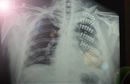

Kırık, Çıkkı ve Çatlak Nasıl Ayırt Edilir?Kırık, çıkkı ve çatlak terimleri, genellikle malzeme bilimi ve mühendislik alanında kullanılan, bir malzemenin bütünlüğü ile ilgili durumları tanımlamak için kullanılan kavramlardır. Bu terimlerin her biri, malzemenin fiziksel durumunu ve yapısal bütünlüğünü farklı şekillerde ifade eder. Bu makalede, kırık, çıkkı ve çatlak kavramları detaylı bir şekilde ele alınarak, aralarındaki farklılıklar açıklanacaktır. Kırık Nedir?Kırık, bir malzemenin veya yapının, yük veya darbe etkisiyle tamamen parçalanması durumunu ifade eder. Kırık, genellikle iki veya daha fazla parçanın ayrılmasına neden olur ve bu durum, malzemenin işlevselliğini kaybetmesine yol açar. Kırıklar, aşağıdaki gibi çeşitli şekillerde sınıflandırılabilir:

Çıkkı Nedir?Çıkkı, bir malzemenin yüzeyinde meydana gelen, ancak tam bir ayrılma durumuna yol açmayan yüzey hasarını ifade eder. Çıkkılar, genellikle yüzeyde görünür bir deformasyon oluşturur, fakat malzemenin bütünlüğü büyük ölçüde korunur. Çıkkılar, malzemenin dayanıklılığını ve performansını etkileyebilir, ancak genellikle acil bir onarım gerektirmez. Çıkkıların bazı özellikleri şunlardır:

Çatlak Nedir?Çatlak, bir malzeme içinde meydana gelen, ancak yüzeydeki bütünlüğü bozmayan bir deformasyon türüdür. Çatlaklar, genellikle malzemenin iç yapısında, stres veya gerilme sonucunda oluşur ve çeşitli boyutlarda ve şekillerde olabilir. Çatlaklar, malzemenin dayanıklılığını azaltabilir ve zamanla büyüyerek kırıklara yol açabilir. Çatlakların bazı özellikleri şunlardır:

Kırık, Çıkkı ve Çatlak Arasındaki FarklarKırık, çıkkı ve çatlak arasındaki temel farklar, bu durumların malzeme üzerindeki etkileri ve yapısal bütünlük ile ilgili farklılıklar içermektedir. Aşağıdaki tabloda bu farklar özetlenmiştir: